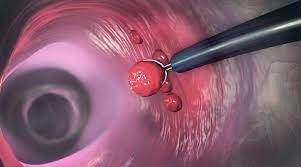

Constituimos una nueva generación de médicos gastroenterólogos en Puebla, altamente capacitados y certificados dentro de la gastroenterología nuestro objetivo es la aplicación de las más altas tecnologías para el diagnóstico y tratamiento eficaz de las enfermedades de esófago, estómago, hígado, vía biliar, páncreas, intestino delgado (duodeno, yeyuno e íleon), intestino grueso (colon) y recto.